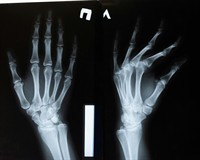

Найчастіше рентгенографію роблять, якщо є підозра на перелом кісток.

Суть дослідження в тому, що рентгенівські промені проходять через тканити тіла. Кістки на плівці матимуть білий колір. Якщо кістка пошкоджена (тріщина чи перелом) на знімку буде помітно "розрив" у білому забарвлені кістки.